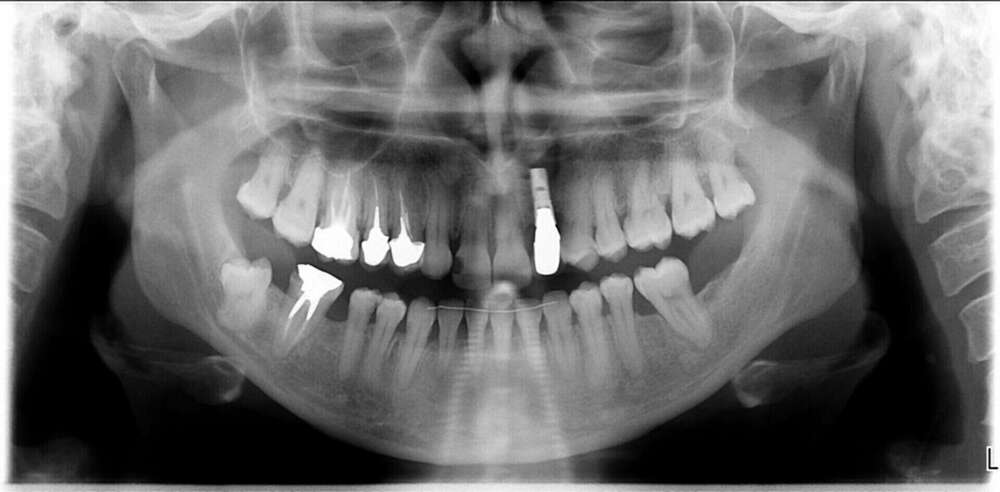

Traitement réalisé chez une femme de 33 ans. La patiente présentait l’absence des deux incisives latérales maxillaires (= agénésies), la canine de lait maxillaire gauche était encore sur arcade et la canine définitive, incluse dans l’os en position haute et oblique. Il a été choisi d’extraire la canine incluse et la canine de lait afin de poser un implant dans ce site. Le traitement orthodontique a permis d’aménager un espace de diamètre identique à la canine droite, de corriger les malpositions et d’améliorer l’engrainement entre les dents maxillaires et mandibulaires. Le traitement a duré 30 mois.